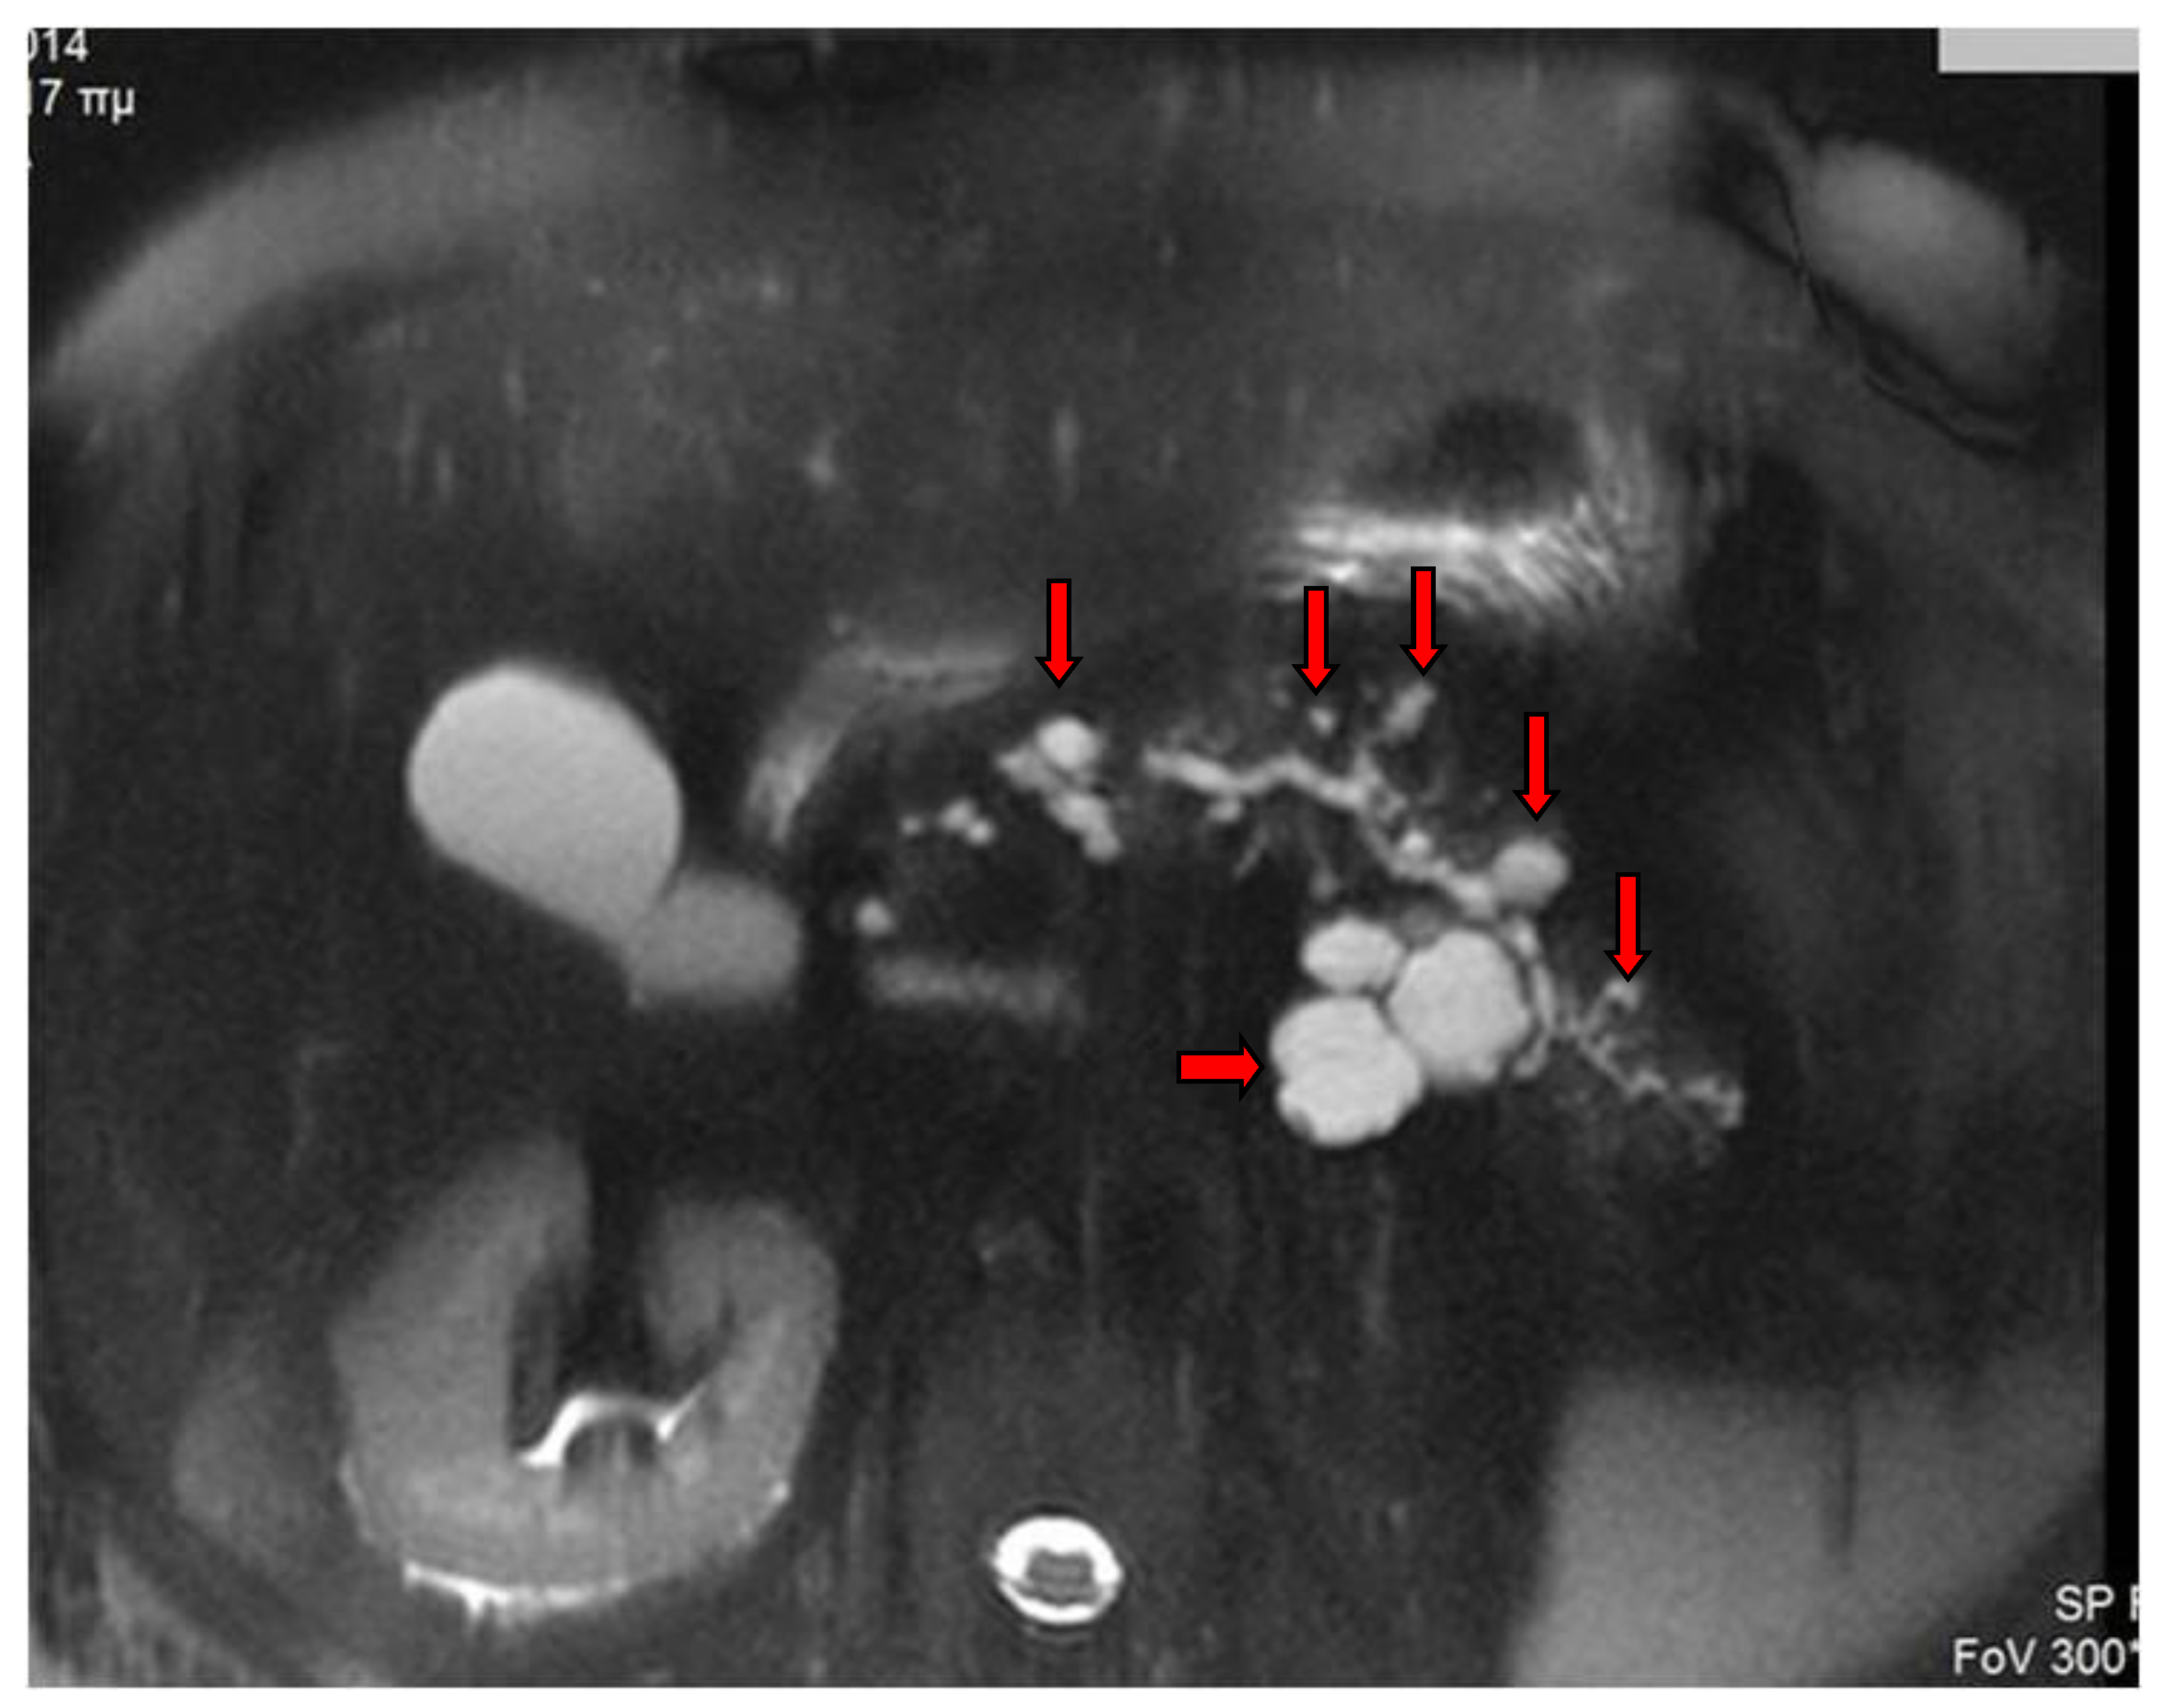

2. Imaging Findings

- Yoon, L.S.; Catalano, O.A.; Fritz, S.; Ferrone, C.R.; Hahn, P.F.; Sahani, D.V. Another dimension in magnetic resonance cholangiopancreatography: Comparison of 2- and 3-dimensional magnetic resonance cholangiopancreatography for the evaluation of intraductal papillary mucinous neoplasm of the pancreas. J. Comput. Assist. Tomogr. 2009, 33, 363–368. [Google Scholar] [CrossRef]